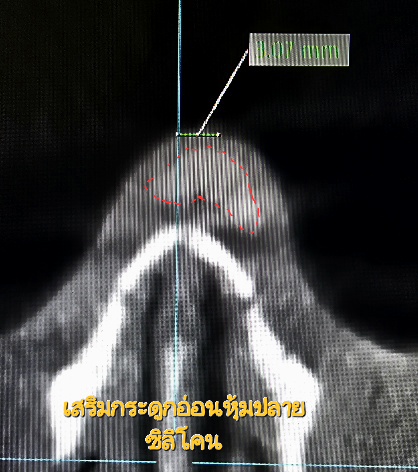

4 เสริมกระดูกอ่อนจริงไหม คุณว่าจมูกที่เสริมมาของคุณเป็นกระดูกอ่อนทั้งหมดจริงๆเหรอ เราตรวจให้ได้ เพราะมีความเข้าใจที่ผิดว่าจมูกสวยๆของฉันปลอดซิลิโคน เป็นกระดูกอ่อนทั้งหมดนะ ไม่อักเสบ,ไม่ทะลุแน่นอน100% หารู้ไม่ว่าเข้าใจผิดมาตลอด หลายเคสที่มาตรวจพบว่าที่จริงมีกระดูกอ่อนแค่ที่ปลายจมูก ไม่ใช่ทั้งหมดอย่างที่คิดไว้

1 กระดูกอ่อน เห็นได้ไม่ชัดเท่าซิลิโคน โดยเฉพาะกระดูกอ่อนซี่โครงที่นำมาทำปลายทั้งดุ้นเช่นตัวอย่างรูปบน การตรวจด้วยเครื่องเอกซเรย์คอมพิวเตอร์ความละเอียดสูง อาจให้ข้อมูลได้ไม่ชัดเจนเท่ากับซิลิโคน แต่ถ้าเป็นกระดูกอ่อนหรือเนื้อเยื่อเทียมหุ้มซิลิโคน การตรวจด้วยเครื่องเอกซเรย์คอมพิวเตอร์ความละเอียดสูงสามารถทำได้ เพราะทรงจมูก ความเอียงเราสามารถบอกได้ด้วยซิลิโคน